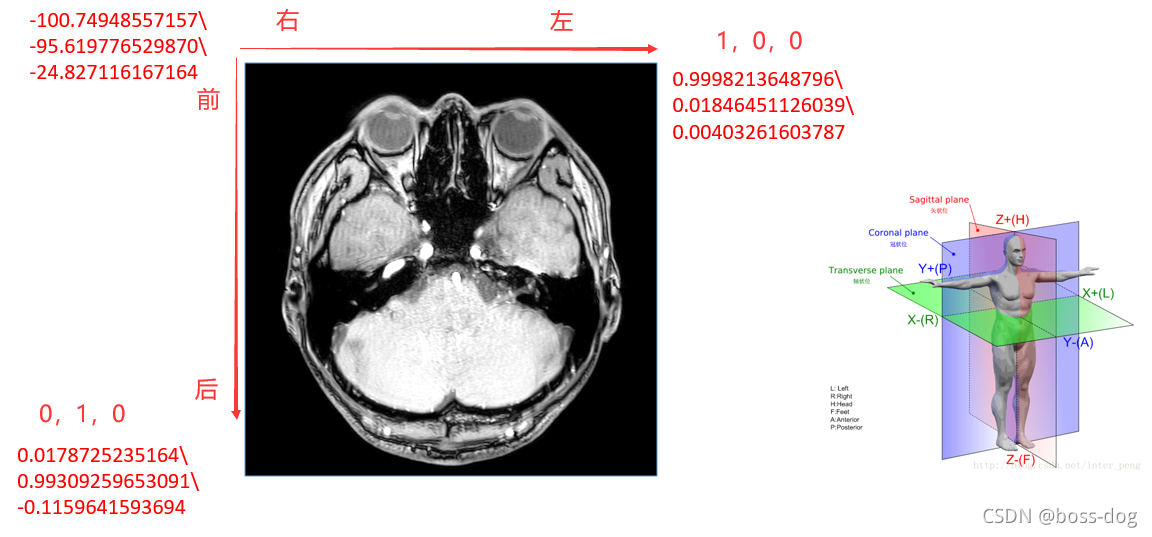

Image Orientation-5

(0020,0037) 的前三个数字代表分别代表行向量(行递增方向)和X,Y,Z轴夹角分别的余弦值(Cosine),后三个数字分别代表列向量(列递增方向)和X,Y,Z轴夹角分别的余弦值。这样就能精确计算出该张影像中每一个像素点在坐标系中的位置,对于多排螺旋CT产生的影像序列来说,这个意义尤其重大。

- 横断面:(1,0,0)(0,1,0)

举例

如上图所示,可以直观地看到鼻子和两个眼睛,基本上可以判断是轴状位的图。红色数字表示为图片中左上角、右上角、左下角三个点的坐标。

水平方向上,图片右上角这个点可以近似的看成(1,0,0),则表示图片上左上角到右上角表示的方向为从右向走,则就判定为图片上左边那个眼睛是右眼,图片上右边那个眼睛是左眼。

竖直方向上,图片左下角的这个点左边近似的看出(0,1,0),表示向后的。